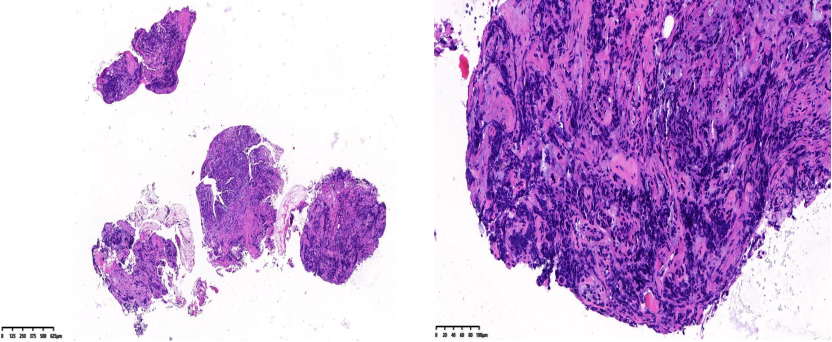

胸水HE染色:见分化差的癌细胞,倾向于分化差的腺癌。

胸水免疫细胞化学染色:CK7(+),TTF-1(-),Ber-EP4(+),Syn(+),INI-1(+),BRG1(-),考虑Smarca4缺失型非小细胞肺癌(Smarca4-dNSCLC)。

病理: HE染色显示支气管黏膜内见分化差的癌浸润,部分组织挤压明显,细胞形态难以辨认。

IHC染色:CKpan (+),CK7(+),BRG1(-),TNI-1(+),Syn(+),CgA(-),TTF-1(-),p40(-),LCA(-),Ki-67(+75%),PD-L1(SP263)(TC:1%)。